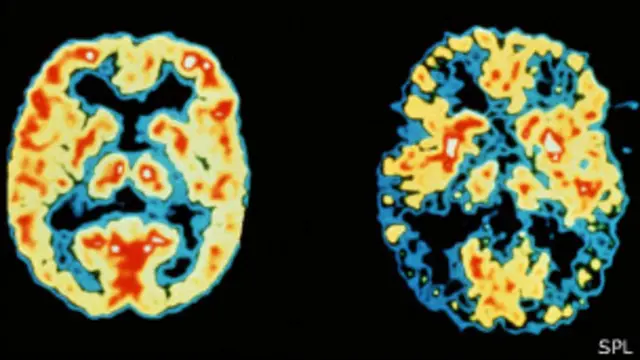

Fuente de la imagen, SPL